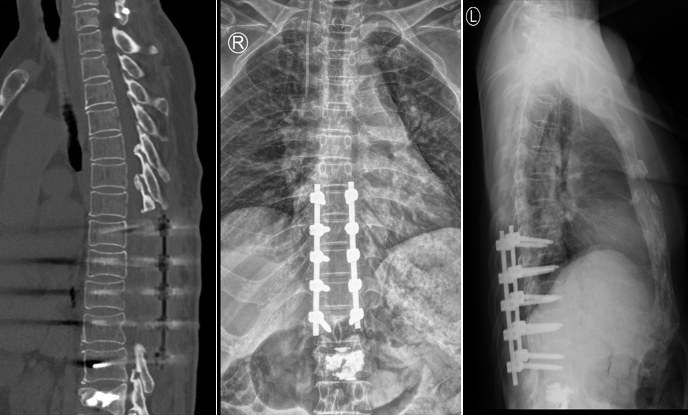

王阿姨近几年来时常感觉双下肢麻木,行走不稳,容易跌倒。王阿姨最近一次摔倒后,出现腰部剧痛、双下肢无力、行走困难的症状,家属立即带着王阿姨来到独墅湖医院骨科姜为民主任诊室就医。经查CT及MR显示:患者 L1压缩性骨折,T5-T12后纵韧带骨化。

L1骨折,合并胸椎管狭窄症

姜主任仔细查体后,确诊患者为“L1骨折,胸椎管狭窄症”。考虑到王阿姨年岁高,手术创伤性大,姜主任决定将治疗方案拆分成两个步骤,第一次手术行“胸椎椎板切除减压术+椎弓根钉内固定术+经皮椎体球囊后凸成形术”,第二次行“内镜下胸椎椎板切除减压术+黄韧带切除术”。

T8-T12椎板切除减压、L1骨水泥强化